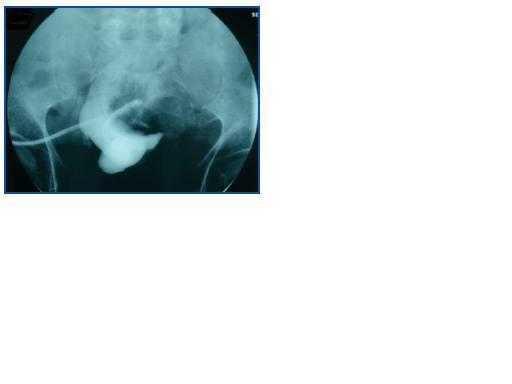

Por decisión del paciente, se implantó de nuevo catéter para diálisis peritoneal mes y medio después de su retirada (TAC abdominal: sin alteraciones). El procedimiento fue realizado por cirugía general, evidenciando adherencias laxas que se liberan. Al mes de la implantación, se objetiva dificultad de drenaje, por lo que se realiza peritoneografía (50 ml de iobitridol 300 mg/l), donde se observa la presencia del contraste limitado a una pequeña cavidad (figura 1).

Ante estos resultados, se decide transferencia a HD y retirada de catéter peritoneal, donde se observa que está totalmente bloqueado por adherencias de epiplón.

Tras 15 días de la implantación, se objetiva disfunción de catéter peritoneal con dificultad tanto para la infusión como para el drenaje. En la peritoneografía se objetiva una imagen de similares características al caso previo (figura 2).

Figura 1.